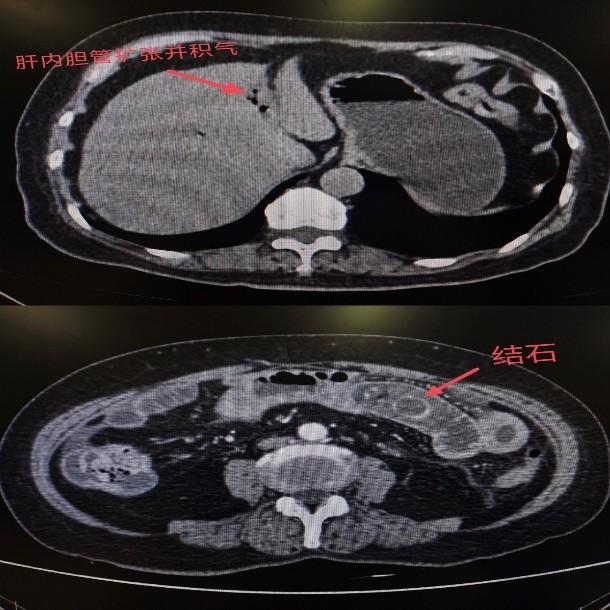

普外科周亮主任接诊后,通过腹部CT检查确诊:李阿姨的胆囊已发生穿孔,一枚结石从破口处掉入小肠并嵌顿,形成机械性肠梗阻,局部肠壁已出现明显水肿、炎症。考虑到患者年龄较大、病情复杂,医生先尝试保守治疗,但经过一周的禁食、胃肠减压、抗感染等措施后,结石仍未排出,肠梗阻症状持续存在。

为避免病情进一步恶化,周亮主任团队与家属充分沟通后,制定了“分步处理、先急后缓”的手术方案。12月16日,医生为李阿姨实施小肠切开取石术,成功取出三枚结石,其中最大的一枚直径约5厘米,呈鸡蛋大小。术后,李阿姨腹痛症状迅速缓解,在医护团队的精心照料下恢复良好,已顺利出院。周亮主任表示,待患者身体完全康复后,还需择期进行胆囊切除术,从根源上避免结石复发。